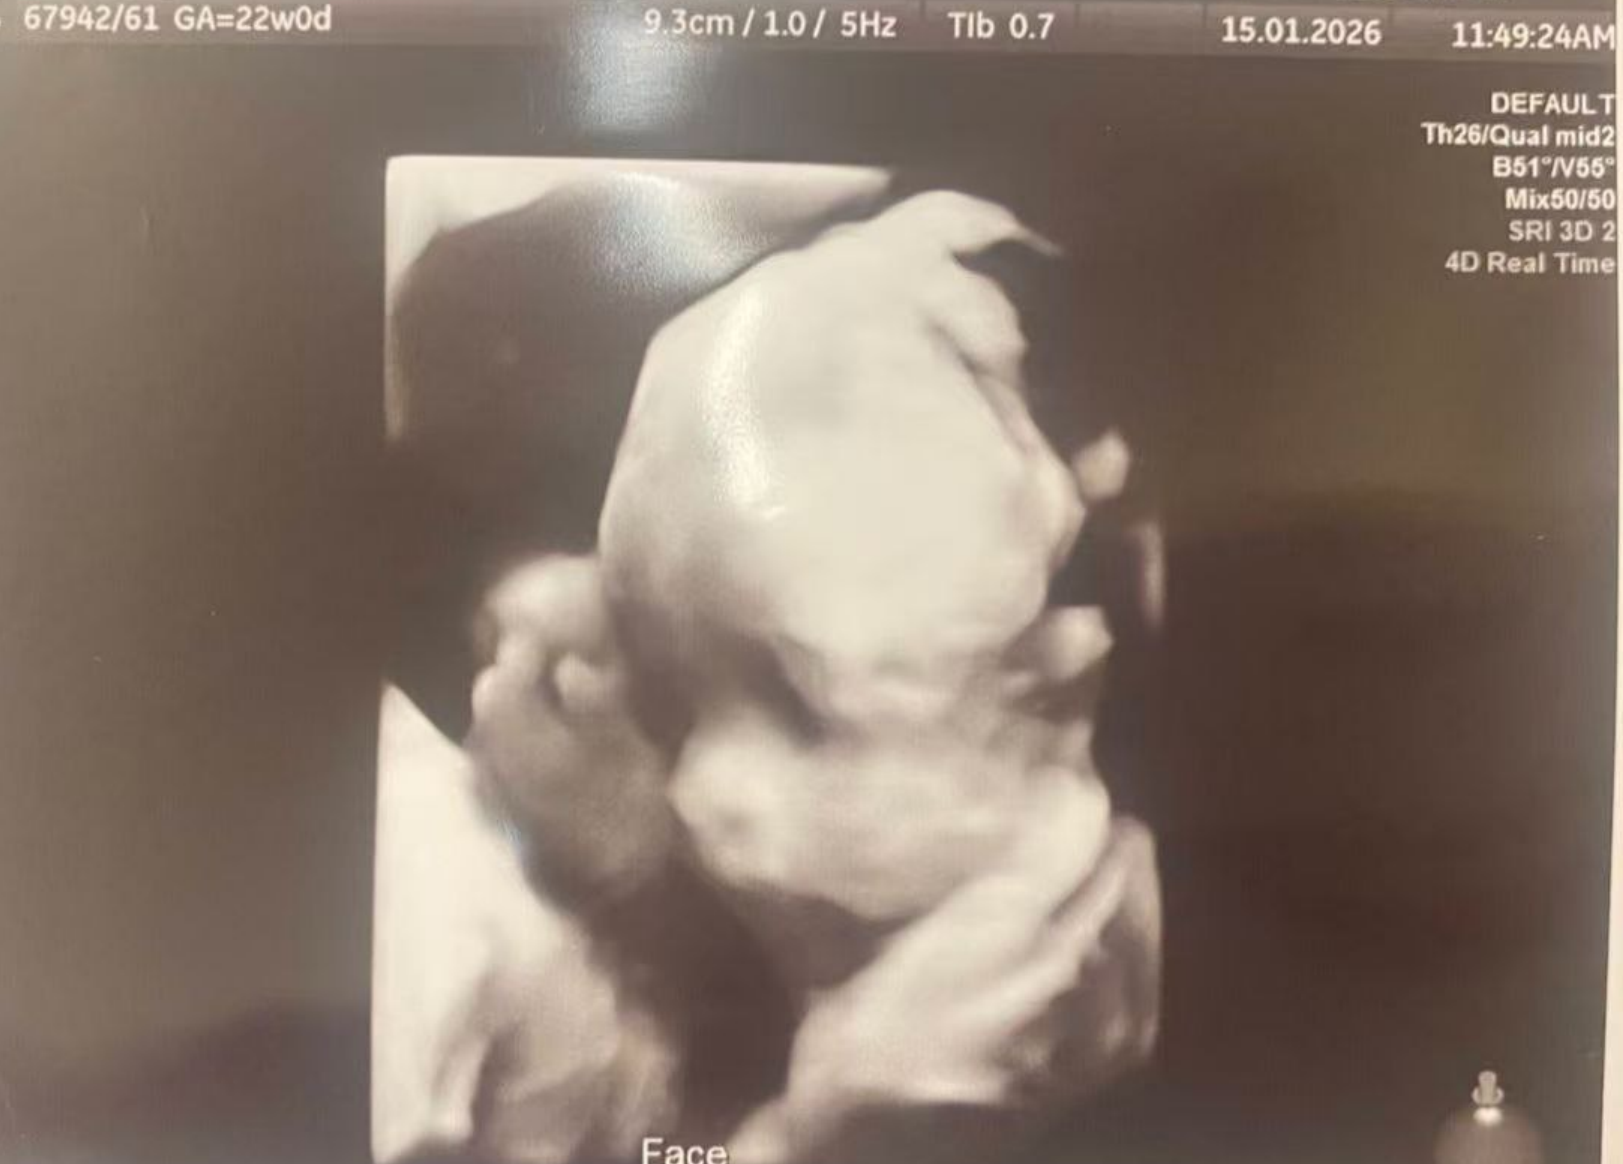

2月14日,孕24週,四維大排畸順利通關!

1月15日完成四維排畸檢查,

結果顯示未見異常,各項發育指標正常。

階段性檢查順利通過,母嬰狀態良好,

感謝關心,繼續穩穩前行,期待相見。